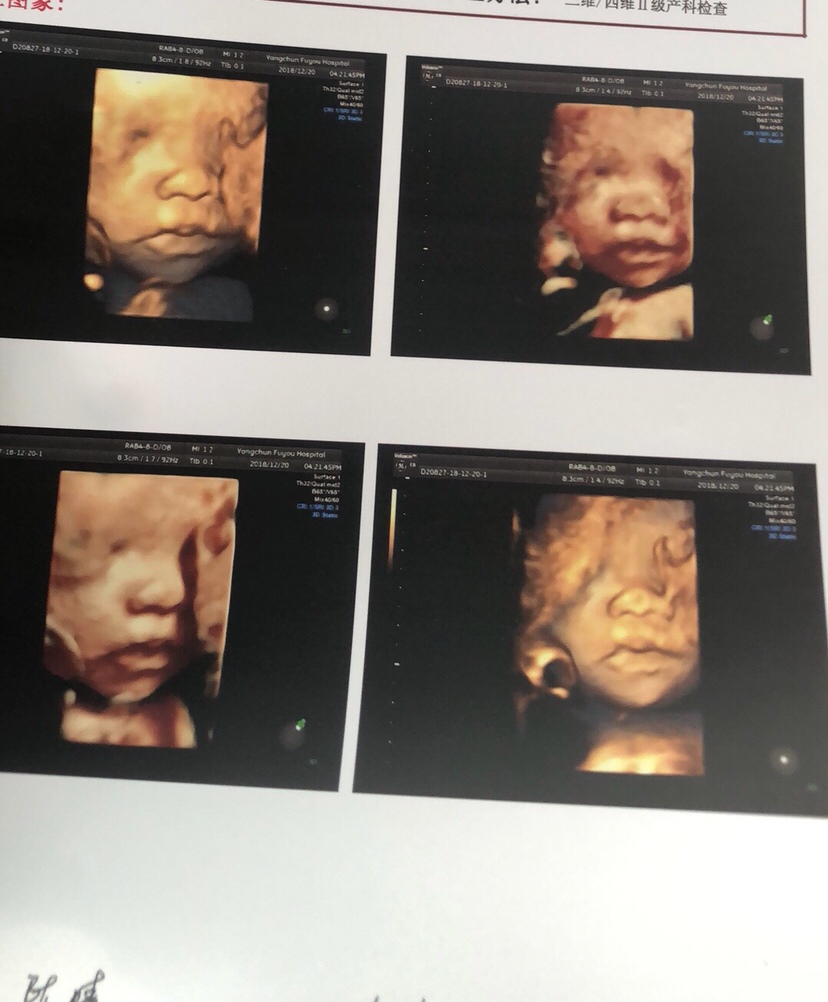

孕13周+5天

接腹中健康女宝